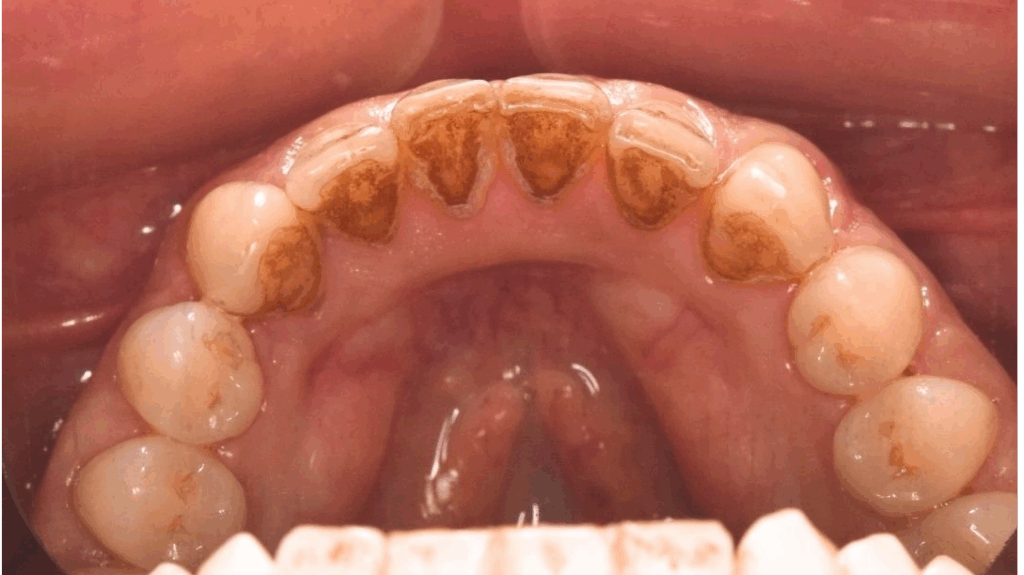

În imaginea de mai jos putem observa depozite de tartru supra / subgingival si coloratia accentuata a dintilor. In aceasta situatie se recomanda efectuarea detartrajului dentar, periajului si al airflowului. O metodă eficientă și minim invazivă, care nu doare, este GBT (GUIDED BIOFILM THERAPY) / EMS. Acesta este cel mai bun concept de igienizare și prevenire dentară din lume, dezvoltat în Elveția.